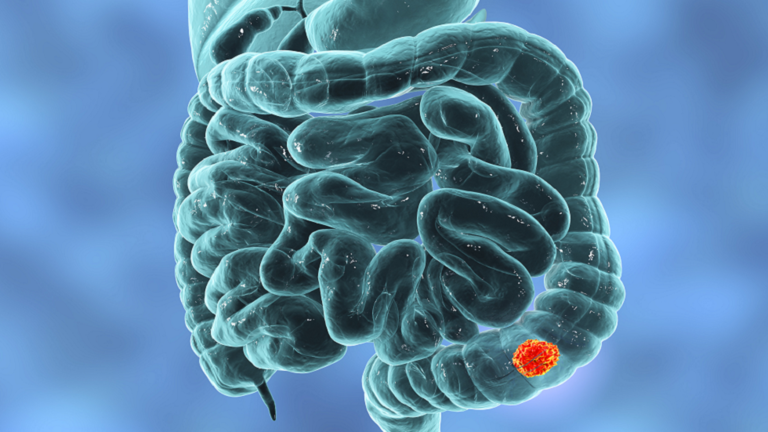

رام الله-نساء FM- تحدثت إحدى الأمهات علنا عن أعراض سرطان القولون لديها لإلهام الناس وتوعيتهم حول صحتهم عندما يتجاهلهم الأطباء.

وكشفت شيري رولينز، أنها تمتعت دائما "بصحة جيدة". وعلى الرغم من وفاة والدها بسرطان الأمعاء، المعروف أيضا بسرطان القولون، في أوائل الخمسينيات من عمره، إلا أنها لم تصدق أن الأمر نفسه يمكن أن يحدث لها.

لسوء الحظ، انتهى الأمر بتشخيص إصابة رولينز، وهي أم لطفلين، بالمرض المميت مرتين.

وكتبت: "تبين أنها المرحلة الرابعة من سرطان القولون الذي انتشر إلى كبدي. وتم تشخيصي بالحالة في أوائل عام 2018".

وكانت شيري على حق حيث انتهى الأمر بتشخيص إصابتها بورم في المستقيم. وهذه المرة، كان الورم أكبر من المتوقع، وانتشر في قاع حوضها.